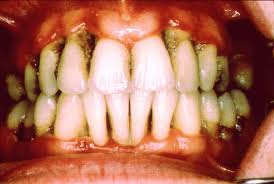

歯周病とは古くは歯槽膿漏といい、日本人の成人の約8割がかかっているといわれます。 歯肉に炎症が起こり、放っておくと膿が出てきたり、口臭がひどくなり、最後には歯が抜け落ちてしまう病気です。虫歯により抜歯となるケースより歯周病により抜歯となる事のほうが断然多いのです。歯周病の進行は、むし歯と違い、重症になるまで痛み無く進むことが多く、そのため「静かなる病気」とも呼ばれています。また、普段の生活習慣が影響することもあり「生活習慣病」の一つに分類されています。最近では、全身の病気(糖尿病、心臓病、早産、低体重児、肺炎)との関連の可能性も言われており無視できない怖い病気との認識が必要なようです。

《 歯周病のチェックポイント 》● 歯肉が赤く腫れてきた

● 歯肉から出血することがある

● 口臭がある

● 歯と歯の間に隙間ができてきた

● 歯肉がさがって歯が長く見える

● 歯がグラグラしてきた

● 歯肉になんとなく違和感がある

みなさんはどうでしたか?チェックポイントに1つでも当てはまる方は歯周病である可能性が高いです。